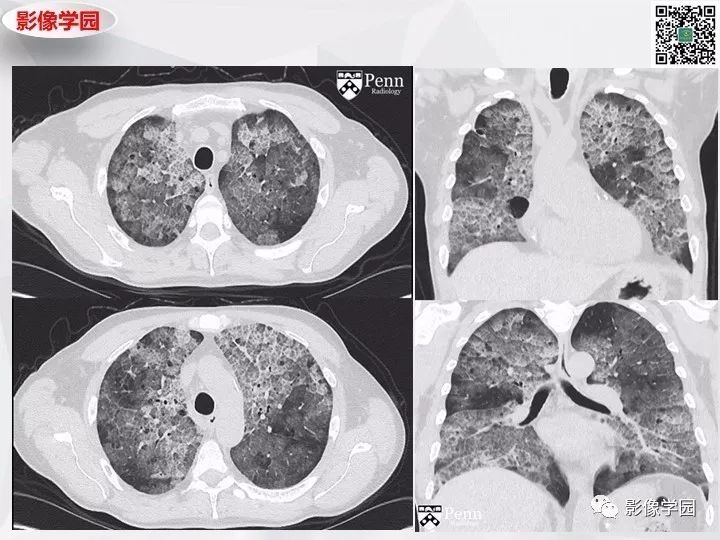

Findings

Diagnosis: Pulmonary alveolar proteinosis

The patient underwent bronchoalveolar lavage, which demonstrated milky and turbid fluid with thick sediment. Cytology demonstrated large foamy macrophages. Serum antigranulocyte-macrophage colony-stimulating factor (anti-GM-CSF) autoantibodies were positive.